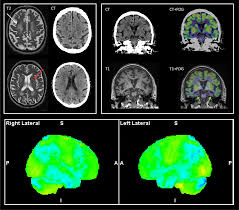

반면 자기공명영상인 MRI는 강한 자석과 전자기파를 통해 촬영하는데 강한 자기장이 발생하는 통 안에서 인체에 해가 없는 고주파를 투여, 공명되는 전자파를 측정한 영상으로 질병을 진단한다고 한다. 또한 MRI는 종·횡단면을 모두 확인할 수 있다는 장점이 있다고 한다.

따라서 더욱 세밀하고 정확한 검사가 가능하며, CT검사로 찾아내지 못하는 질병을 발견할 수 있고, CT에 비해 정밀한 3차원 영상을 볼 수 있어 다양한 각도에서 질환을 판독하는데 용이하다고 한다. 주로 뇌, 신경, 혈관, 근육, 인대 등의 질병을 검사하고 진단한다고 한다.

그러나 MRI는 CT에 비해 출혈, 골절 등의 병변이 잘 보이지 않는 경향이 있어 응급상황에서는 최초 검사로 CT를 우선 시행하는 경우가 많고 세밀한 판독을 위한 추가 정밀검사 방법으로 MRI를 시행하게 된다고 한다. 한편 MRI는 근육파열, 신경손상 등을 확인하는데 효과적이고 특히 디스크 판독에도 탁월하다고 한다.